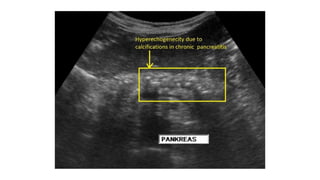

• Investigations

-pancreatic calcification on AXR

-features in CT, MRI, ECRP, EUS

• Calcification within pancreas